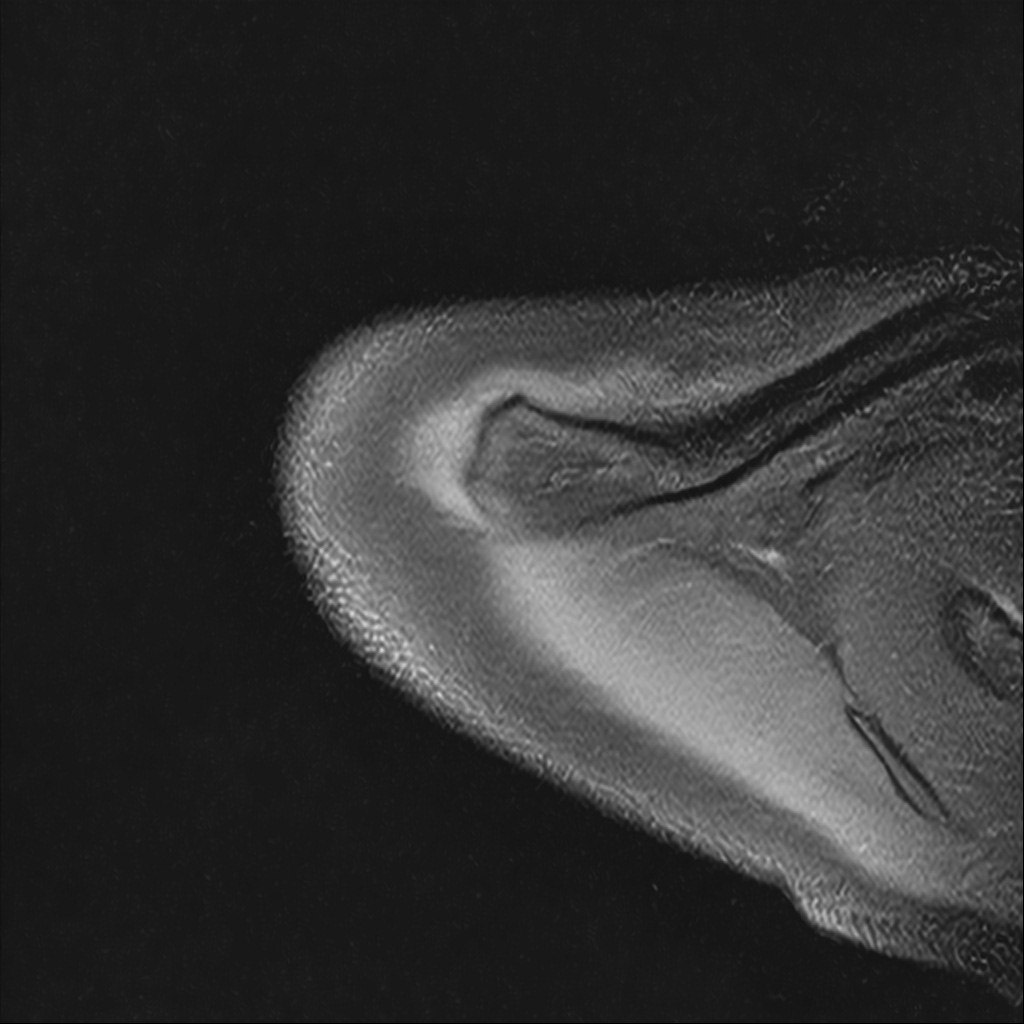

Mri 단면 영상으로 보아 어깨 관절 부위에서 이상 신호가 관찰되고 이는 관절 와순 파열의 가능성을 시사할 수 있습니다.

하지만 이영상만으로 정확한 진단은 불가능하고 정밀한 판단을 위해선 전체 시퀀스와 영상의학과 전문의의 공식판독이 필요합니다 특히 와순 파열은 위치와 동반 병변에 따라 해석이 달라집니다!